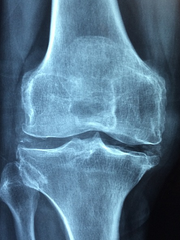

무릎 관절에 좋은 음식에 대해 알아보도록 하겠습니다. 무릎 관절은 우리 몸에서 가장 중요한 관절 중 하나로, 우리 몸의 움직임에 매우 중요한 역할을 합니다. 하지만 평소에는 중요성이 자주 간과되는 부위이기도 합니다. 무릎 관절은 일상적인 활동에도 계속해서 스트레스가 더해지고 우리가 아무렇지 않게 하는 활동으로 인해 엄청난 압력이 가해져 손상이 되기도 하는데 스스로 재생하는 능력이 제한적이므로 신경을 쓰지 않고 막 쓸 경우 나중엔 수술적 치료 말고는 방법이 없는 상황이 될 수 있습니다. 따라서 아직 무릎이 괜찮을 때 무릎 관절 건강을 유지하는 것이 중요하고, 우리의 식단에 몇 가지 특정 식품들을 추가함으로써 무릎 관절 건강을 개선하고 유지하는 데 도움을 줄 수 있습니다.

무릎 관절염의 증상은 어떤 것들이 있을까요?

1. 무릎 부위에 통증이 있습니다. 통증은 걷거나 서을 때, 계단을 오르내리거나 앉았다 일어날 때, 날씨가 변할 때 등에 심해집니다.

2. 무릎 부위에 부종이 있습니다. 부종은 염증과 출혈로 인해 생기며, 만지면 따뜻하고 아프게 느껴집니다.

3. 무릎 부위를 움직일 때 딸깍거리는 소리가 납니다. 소리는 연골이 닳아 없어진 부분에서 뼈와 뼈가 마찰하면서 나는 것입니다.

4. 무릎 부위의 움직임이 제한됩니다. 움직임이 제한되면 무릎을 구부리거나 펴기 어렵고, 자세를 바꾸거나 걸음걸이에 어색함을 느낍니다.

5. 무릎 부위의 모양이 변합니다. 모양이 변하면 무릎이 비대칭적으로 보이거나, 안쪽이나 바깥쪽으로 꺾여 보이거나, 앞쪽으로 돌출되어 보입니다.